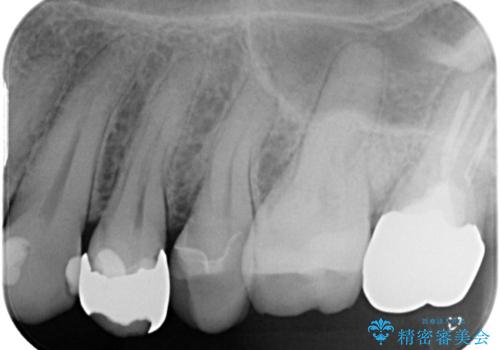

- 金属の詰め物が外れた状態で長期間過ごされた患者様が、歯を治したいとのことで来院されました。良好な長期予後が期待でき、歯質をできるだけ残せるセラミック治療を即日で行いました。

治療途中で虫歯も綺麗に除去しています。術後経過良好で、患者様も満足されています。他にも治療が必要な虫歯がありますので、順を追って治療する予定です。

今回の治療では、MarkⅡというセラミックのブロックを削り出して使用しています。従来からある、手で築盛して製作するタイプの修復物には気泡が発生しやすいのですが、これは歯に力がかかった際に破断点となりインレーが割れてしまう一因となります。MarkⅡブロックには気泡がありませんので、割れてしまうリスクを減らすことができます。